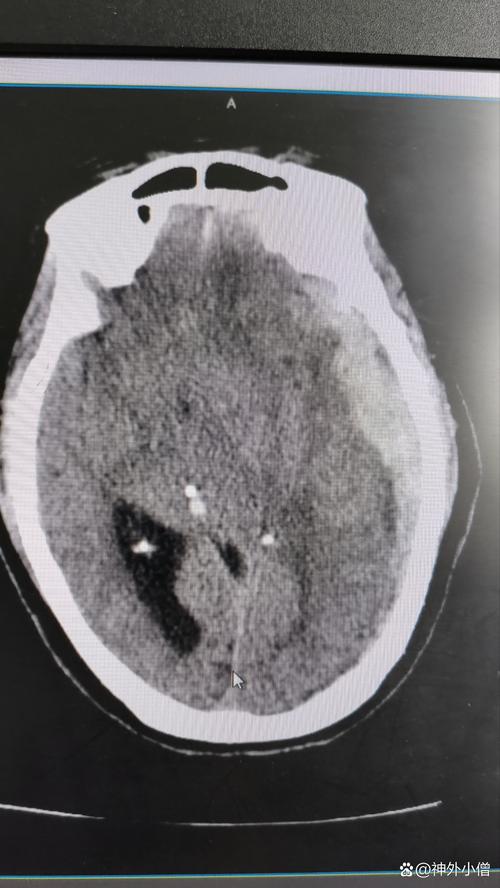

颅脑损伤 → 脑疝 → 脑梗

这是一个病情急剧恶化的典型过程,下面我们逐一分解。

核心问题: 无论是血肿还是水肿,都会导致一个致命的问题——颅内压增高。

脑疝

是什么? 脑疝是颅脑损伤(或其他导致颅内压增高的疾病,如肿瘤、中风)最危险的并发症,是危及生命的信号。

为什么会发生?(病理生理) 我们的头颅是一个坚硬的骨盒子,里面容纳着大脑、脑脊液和血液,大脑被硬脑膜等结构分隔成不同的“房间”(如大脑半球、小脑、脑干)。

- 颅内压增高时: 颅腔内容物(血肿、水肿的脑组织)不断增多,但颅骨的容积是固定的,为了寻找“生存空间”,压力最高区域的脑组织就会被挤压、移位,穿过颅骨的天然孔道或缝隙,挤到压力较低的区域去,这个过程就像把一个装满东西的硬皮箱,强行盖上盖子,里面的物品会从缝隙中挤出来一样。

这个过程就是“脑疝”。

- 小脑幕切迹疝(颞叶疝): 最常见,大脑半球的颞叶海马钩回被挤压,穿过小脑幕的切迹,压迫下方的中脑。

- 枕骨大孔疝(小脑扁桃体疝): 最凶险,小脑扁桃体被挤压,穿过枕骨大孔,压迫延髓。